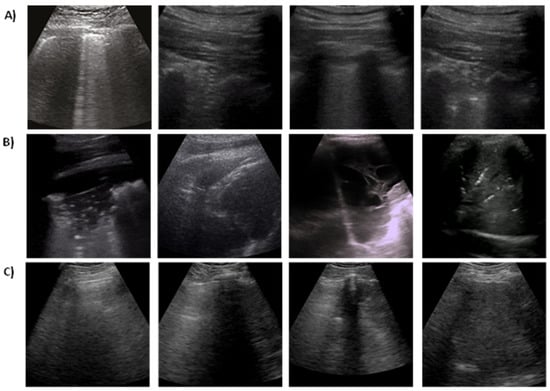

To train and evaluate the proposed method, a public and open-source LUS dataset is used, which is known as the POCUS dataset. The dataset consists of image and video samples belonging to three classes of infection, namely COVID-19, viral pneumonia, and bacterial pneumonia, in addition to samples from healthy individuals. The dataset contains a total of 261 recordings (202 videos + 59 images) captured from a total of 216 patients with either linear or convex probes. The distribution of samples across different classes is given in more detail in Table 1. Linear probes have high frequency, leading to a superior resolution that enables improved investigation of irregularities near the pleural line [22]. However, the linear probe penetrates the lung tissue less than the convex probe, which could make it hard to tell the difference between B-line artifacts (a major lung artifact) and hidden tissue. The images and videos in the POCUS dataset were aggregated from a variety of sources, such as clinical data obtained from academic ultrasound courses, hospitals, scientific publications, public medical repositories, and health-tech corporations. The complete details of different sources of data in the POCUS dataset can be found in reference [19]. The COVID-19 cases were confirmed by RT-PCR. The dataset is supplemented by a comprehensive metadata file encapsulating the anonymized patient identifier, source URL, source identifier, sex, age, symptoms, pathological manifestations, video frame rate, image resolution, and the total of frames per video. The length and type of videos are a varied (160 ± 144 frames) dataset, whereas they have a frame rate of Hz. Outstandingly, all samples in the dataset were reported to be revised and confirmed by one medical expert with more than 10 years of clinical experience and an academic instructor. Figure 2 shows some examples of 2D ultrasound frames for COVID-19, pneumonia, and healthy patients.

Figure 2.

Examples of lung ultrasound images for different pulmonary diseases: (A) COVID-19, (B) Pneumonia, (C) normal case.